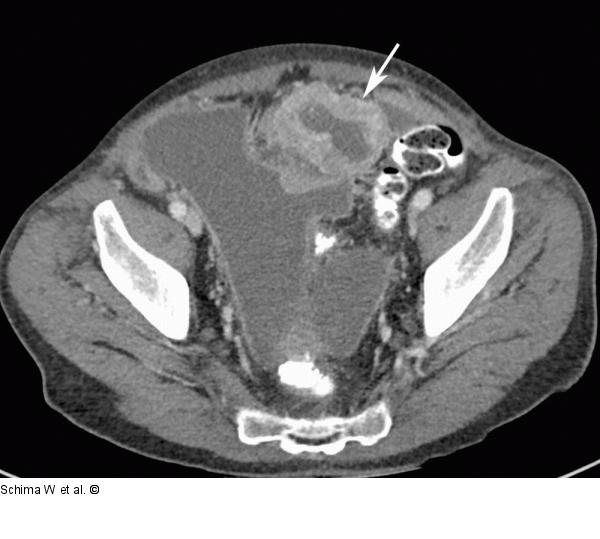

Abbildung 2a: MDCT Die axiale KM-verstärkte MDCT zeigt den ausgedehnten hypervaskularisierten, jedoch zentral nekrotischen Tumor (Pfeil), der mit Dünndarmschlingen verbacken ist. Differenzialdiagnostisch kommt aufgrund der ausgeprägten Vaskularisation das Vorliegen eines neuroendokrinen Karzinoms oder eines GIST infrage. |

Die axiale KM-verstärkte MDCT zeigt den ausgedehnten hypervaskularisierten, jedoch zentral nekrotischen Tumor (Pfeil), der mit Dünndarmschlingen verbacken ist. Differenzialdiagnostisch kommt aufgrund der ausgeprägten Vaskularisation das Vorliegen eines neuroendokrinen Karzinoms oder eines GIST infrage. |